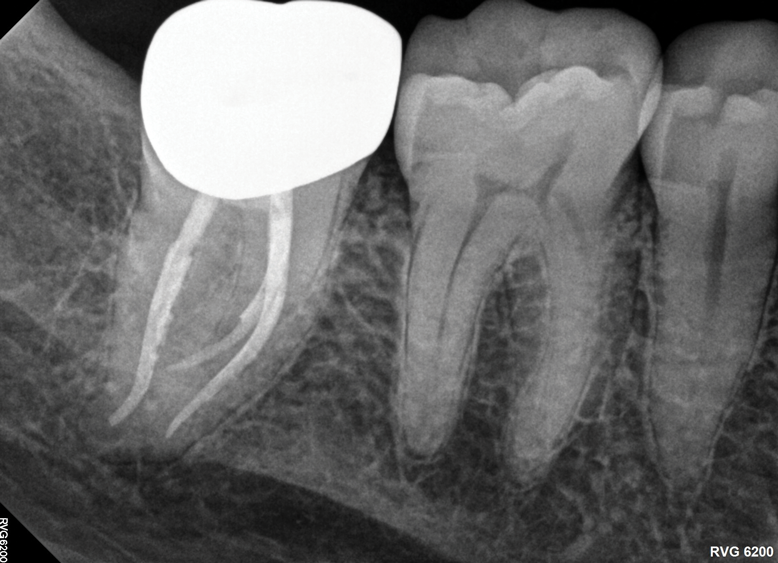

The material used to fabricate a post should be considered as well. Both cast and prefabricated options are available, but there is no consensus regarding the effect of cast versus prefabricated posts on survival rates, and different studies have found opposing results.5,16 The most common materials used in posts are metal and fiber. Both materials have been associated with similar survival rates.17 In teeth with no remaining coronal walls or an absence of ferrule, posts with higher values of elastic modulus, such as fiber posts, have been shown to result in better clinical outcomes when compared with metal posts.18 However, in teeth with at least one remaining coronal wall, restorations with fiber and metal posts demonstrated similar survival rates.18 The choice of which material to use should be based on the specific case and patient factors (Figure 4 and Figure 5).

(4.) Radiographs of teeth treated with prefabricated and custom cast posts, respectively.

Figure 4

(5.) Radiographs of teeth treated with prefabricated and custom cast posts, respectively.

Figure 5